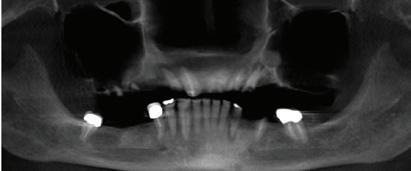

All-On-4 Dental Implants: A Reason To Smile Again

All-on-Four: One Full Arch Of Teeth, Four Dental Implants

To fully understand this remarkable technique for replacing teeth, you should first understand what a dental implant is. An implant is a small titanium screw that fits inside your jawbone and replaces the root-part of a missing tooth. Minor surgery is required to insert the implants. Once the implant is in place, a crown is attached to give you a highly realistic-looking and functional prosthetic tooth.

Here’s where it gets really interesting: You do not need a dental implant for each and every one of your missing teeth. All you need is four precisely placed implants on the top of your mouth, and four on the bottom, to restore your full smile. That’s the beauty of the all-on-four. And because the implant is made of titanium, it has the unique ability to fuse to living bone and function as part of it. So eventually, the dental implant becomes part of the jawbone and serves as a strong, long-lasting foundation for your new teeth.

Besides ensuring that your implants are permanently fixed in place, this bone fusion has another important benefit: it prevents future bone loss in the jaw. This helps to maintain a more youthful facial structure – and better oral health. But perhaps the biggest surprise about the all-on-four is how quickly it can transform your life.